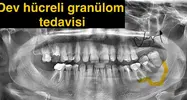

Çene Kistleri